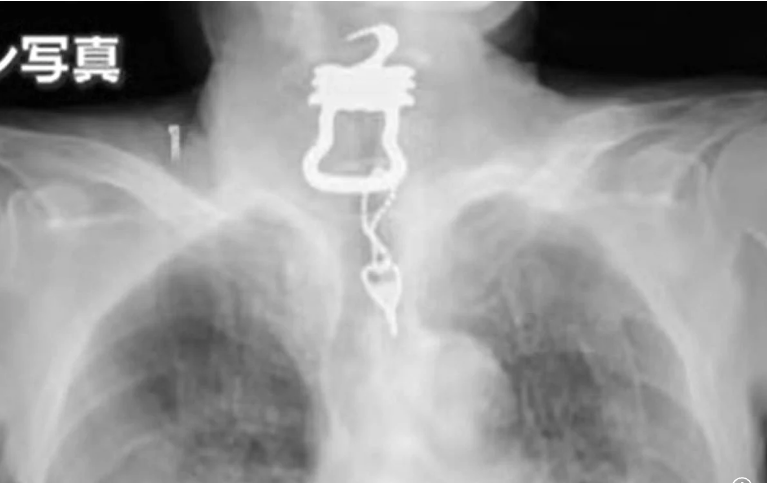

ونُقل كينيتشي أونيشي، 82 عامًا، إلى مستشفى أوساكا في يناير 2022 بعد كسر عظمة صدره إثر سقوطه. وبعد بضعة أشهر، في سبتمبر، اشتكى من ألم في الحلق وشُخِّصت إصابته بفيروس كوفيد-19. ومع ذلك، أظهرت الأشعة السينية على الصدر ظلًا كبيرًا في حلقه، والذي تم تحديده لاحقًا على أنه مفتاح بطول 12 سم متصل بسلسلة مفاتيح.

وقال ابنه البالغ من العمر 55 عامًا، وفقًا لقناة “يوميوري”: “في البداية، تخيلت أنه مفتاح صغير ابتلعه عن طريق الخطأ”. لكن عندما رأيته، صُدمتُ. كان ثقيلًا وشكله غريبًا.” وأوضح “كان المفتاح المعدني، مع سلسلة على شكل أوزة ذات حواف حادة” وهو كما تبين مفتاح ملابس يُستخدم لتأمين بذلة خاصة مصممة لمنع المرضى من العبث بالمعدات الطبية أو الحفاضات، وكان والده، الذي شُخِّص بالخرف الخفيف، يرتدي البدلة أثناء إقامته.